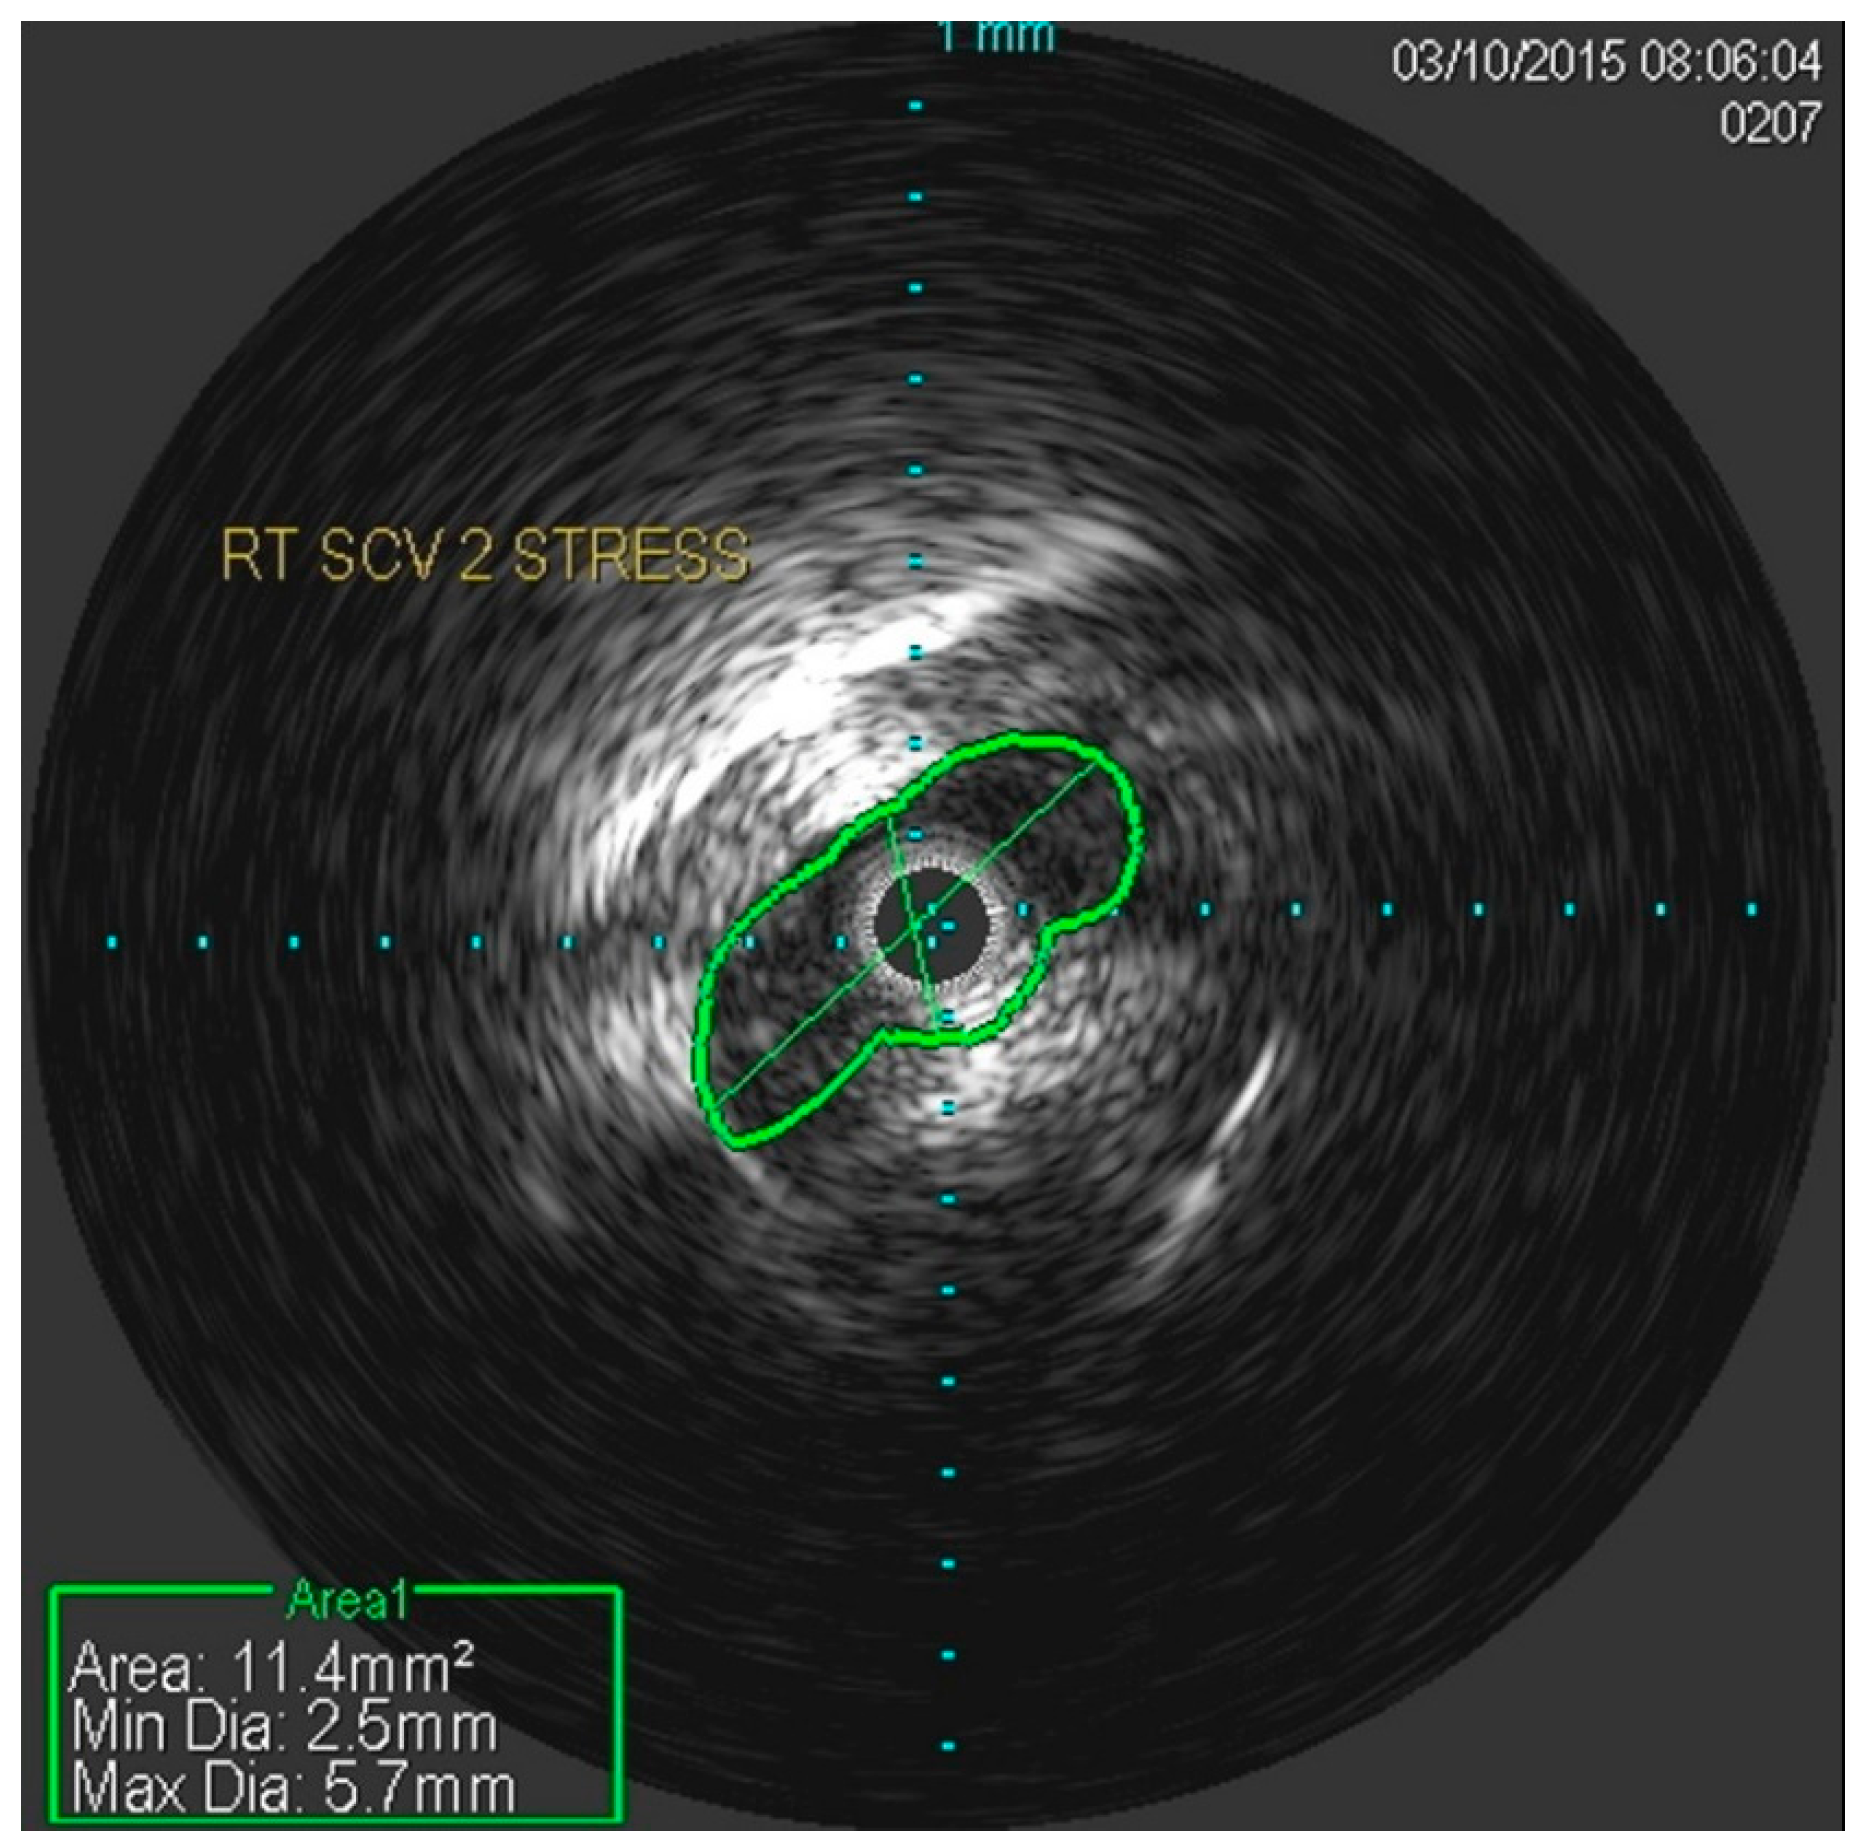

She underwent venography of the right arm venous system which revealed a 70–80% stenosis of the right subclavian vein in neutral position (Figure 1 and Figure 2). The vein was completely occluded in stress position. This was confirmed with intra-vascular ultrasound (IVUS). On IVUS measurements, the neutral position yielded a 74.4% stenosis while the stress position yielded 100% total occlusion (Figure 3 and Figure 4). It was noted that the contralateral vein appeared compressed in the costochondral space as well, though she was asymptomatic.

Figure 3.

Nearly occluded right subclavian vein in stress position as demonstrated by IVUS.